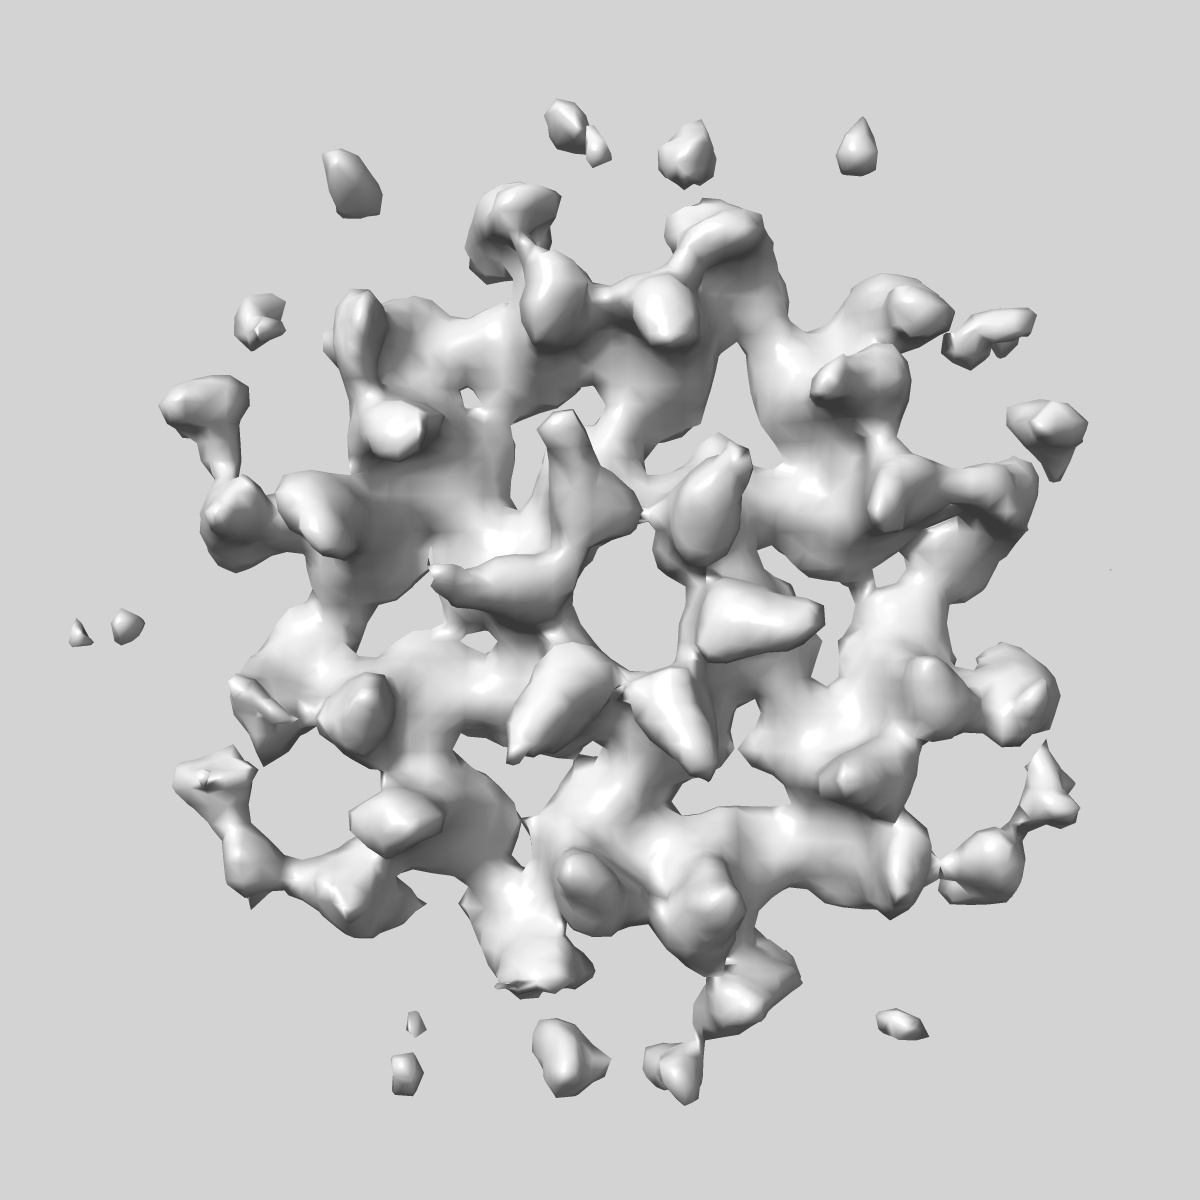

HIV-1 CA hexamer from cytoplasmic capsids (FIB-lamella data of HIV infected macrophages)

Subtomogram averaging

27.7 Å

Sample Organism: Human immunodeficiency virus type 1, NNHIV

Sample: Human immunodeficiency virus type 1, NNHIV

Deposition Authors: Kreysing JP , Welsch S , Turonova B , Beck M

Passage of the HIV capsid cracks the nuclear pore.

Kreysing JP , Heidari M, Zila V, Cruz-Leon S, Obarska-Kosinska A , Laketa V, Rohleder L, Welsch S , Kofinger J, Turonova B , Hummer G , Krausslich HG, Beck M

(2025) Cell , 188 , 930 - 943.e21

PUBMED: 39826544

DOI: doi:10.1016/j.cell.2024.12.008

ISSN: 1097-4172